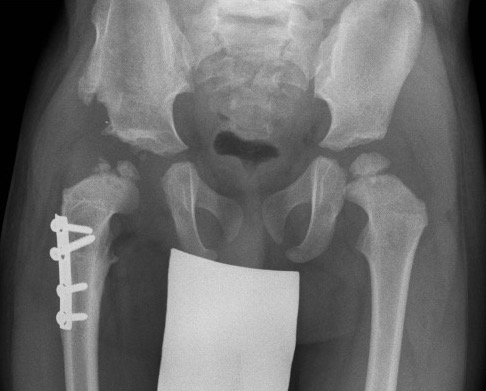

AP X-ray

Timing

AP after 6 months of age when the superior femoral epiphysis becomes ossified

Create 4 quadrants on xray

- Hilgenreiner's Line - horizontal through triradiate cartilages

- Perkin's Line - vertical through lateral edge of bony acetabulum

- superior femoral epiphysis (SFE) should be in inner and lower quadrant

Dislocated hip with smaller superior femoral epiphysis (SFE) and location in the upper outer quadrant

Findings

| Superior femoral epiphysis | Disrupted Shenton's line | Increased acetabular index | Increased head to teardrop distance |

|---|---|---|---|

|

Smaller

In upper/ outer quadrant |

Line along inferior neck

Line inferior border superior ramus |

Angle between Hilgenreiner's line and acetabular line |

Lateral tear drop to medial ossification center |

Normal < 30° DDH > 35° |

Avascular necrosis

AVN of the femoral head on the right